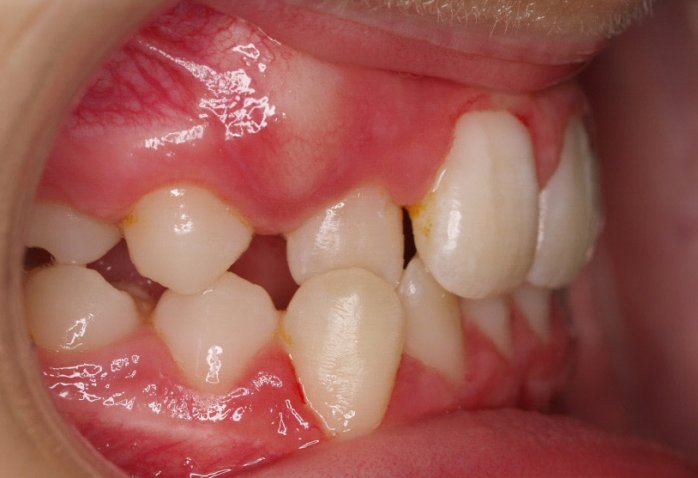

El paciente actualmente ha terminado el tratamiento con brackets y lleva una contención fija de 2-2 en maxilar y 3-3 en mandibular; para complementar también lleva una férula ESSIX durante la noche.